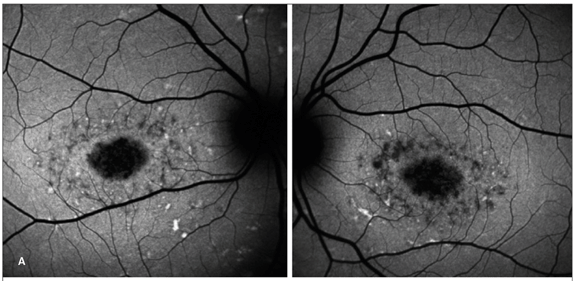

Distrofia de cones

Em seis pacientes com distrofia de cones foi encontrado hipoautofluorescência macular. Em três pacientes, havia halo hiperautofluorescente ao redor da área foveal. E um padrão diferente com desorganização da área macular em apenas um dos pacientes (Figura 4).